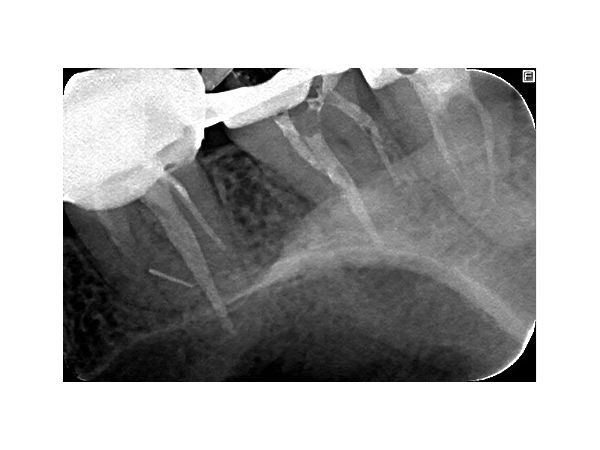

В поликлинике "Наша Клиника-Дент" проведено визиографическое обследование свищевого хода, предварительно в него был введён гуттаперчевый штифт для уточнения локализации воспалительного процесса. Выявлен очаг воспаления в области корней 17 зуба. Также обнаружен участок повышенной плотности, по конфигурации соответствующий фрагменту инструмента в мезиально-щёчном корне 16 зуба.

Для уточнения размеров и локализации очага инфекции пациентке рекомендовано проведение конусно-лучевой компьютерной томографии (КЛКТ). По КЛКТ от 14 марта 2019 в проекции корней 17 зуба обнаружен очаг деструкции с вершиной на мезиальном, дистальном и нёбном корнях, выявлено сообщение с верхнечелюстной пазухой. В области 16 и 18 зубов патологии не выявлено.

После протезирования временной коронкой пациентка не предъявляла жалоб. На контрольной томограмме в сентябре 2019 года наблюдается уменьшение очага деструкции, восстановление дна гайморовой пазухи. Рекомендовано обратиться к врачу-ортопеду для протезирования постоянной ортопедической конструкцией. Осмотр в марте 2020 года.